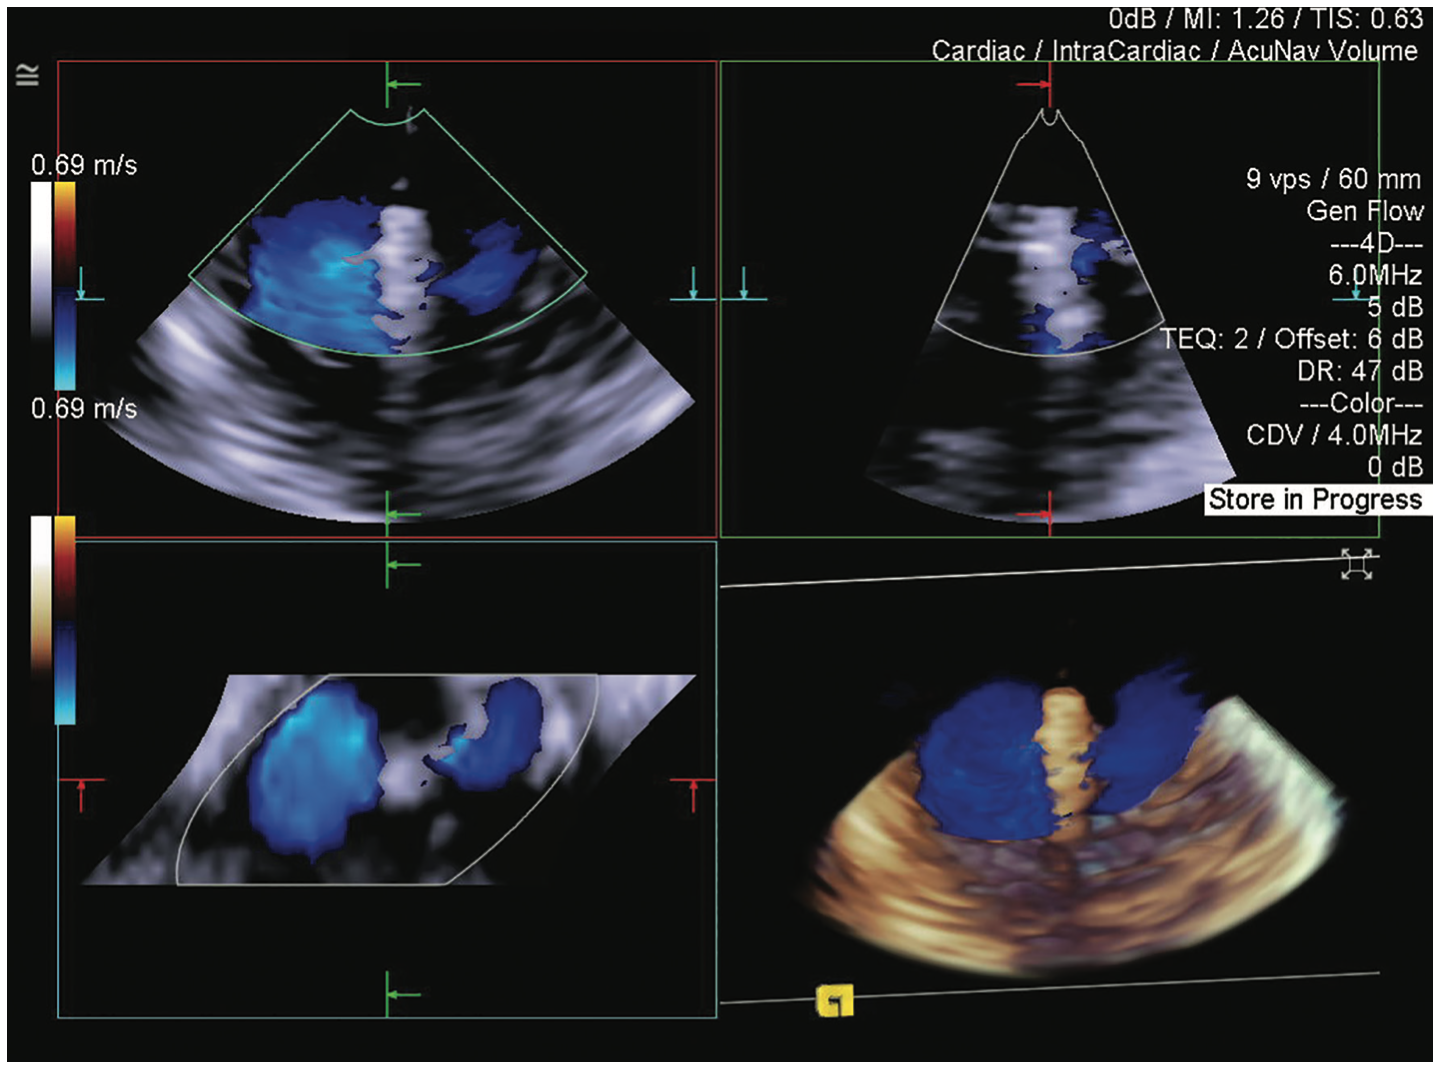

This case of transcatheter edge-to-edge repair (TEER) with a MitraClip device (Abbott) demonstrates how 4D volume intracardiac echocardiography (ICE) catheter imaging (ACUSON AcuNav Volume ICE catheter on the ACUSON SC2000 PRIME ultrasound system, Siemens Healthineers) enables the treatment of patients with severe mitral regurgitation who otherwise would have no options for care.

A 38-year-old female with significant osteogenesis imperfecta, severe scoliosis, and severe myxomatous mitral valve was referred for TEER. An adult transesophageal (TEE) transducer could not be used due to the severe scoliosis, and pediatric TEE imaging was suboptimal for use in the procedure. Preprocedural transthoracic echocardiogram demonstrated severe mitral regurgitation. The 4D ICE catheter assisted with transseptal puncture at the optimal superior and posterior positions, with the circle tool verifying the 4.5 cm distance from the mitral annular plane. Biplane imaging using reference planes with and without color helped guide the device to the optimal position. Physicians were able to treat the patient with relative or absolute contraindication to TEE.